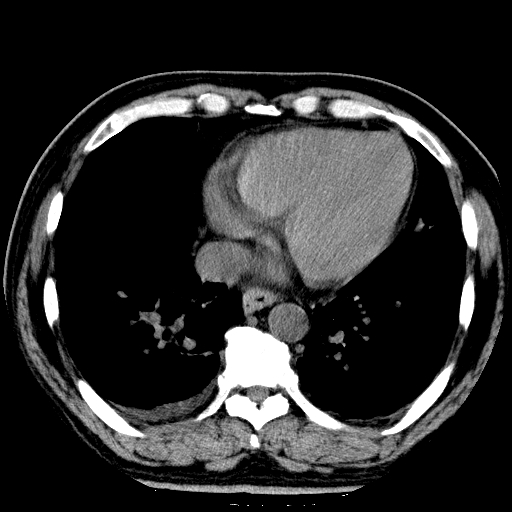

标题: CT21804:男,65岁,咳嗽、咳痰、发热5天。 [打印本页]

男,65岁,咳嗽、咳痰、发热5天。